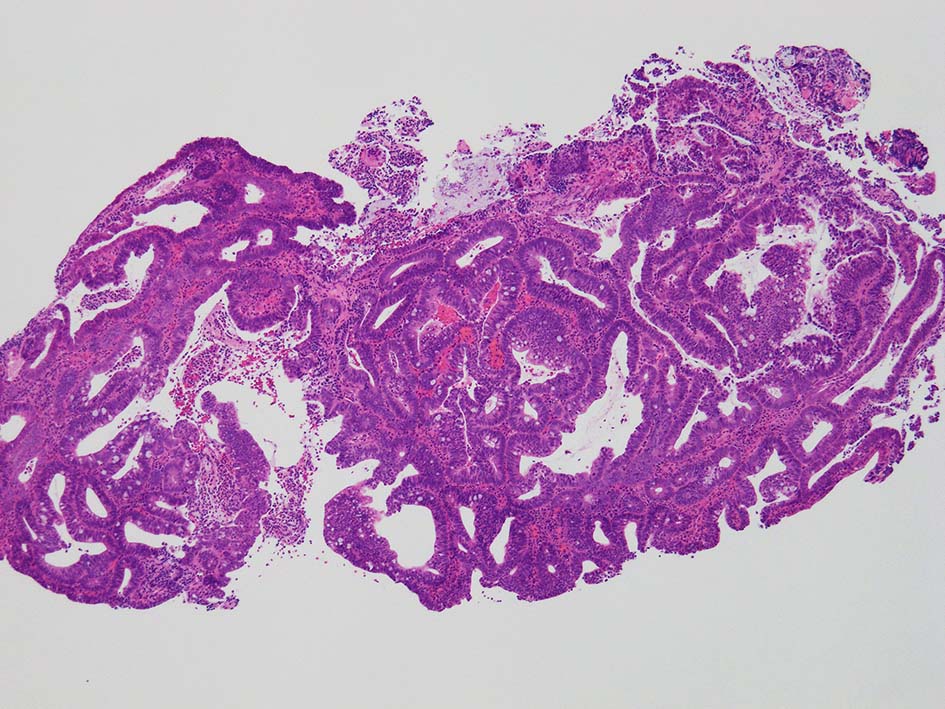

膀胱鏡検査で頸部6時方向に乳頭状腫瘤があり, 膀胱がん疑いで生検をおこなう.

腸管型の腺癌。大腸の高分化腺癌と組織学的に区別は難しい.

desmoplastic fibrosis, 粘液浸潤のみられる組織片にはsig, porのadenocarcinoma浸潤が確認される.

neutrophilic exudate の付着する腸管型腺癌部分. 核はより腫大し円形、vesicularとなっている. 上記腸管型とはCK20, CK7のそまりが異なっていた. 変性のためかもしれない.